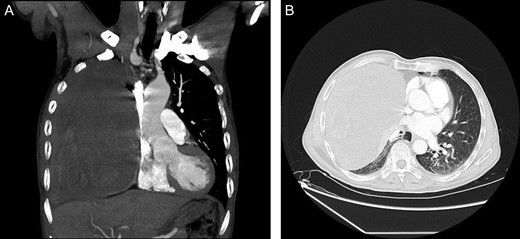

A 68-year-old male presented to our hospital after experiencing exertional dyspnea and shortness of breath for 2 months. He had no other chest complaints, such as cough, hemoptysis or chest pain. His medical history was unremarkable and he had no history of exposure to asbestos. He had no exposure to tobacco. His blood pressure was 136/78 mmHg, pulse was 92 beats/min and respiratory rate was 23 breaths/min. He was afebrile, and oxygen saturation was 94% in room air. Examination of the chest revealed dullness and diminished breath sounds on the right hemithorax. A plain chest X-ray showed a right side huge opacity (Fig. 1). A contrast-enhanced computed tomography (CT) revealed a large heterogeneous mass that almost completely fill the right hemithorax (Fig. 2a and b). CT-guided transthoracic core needle biopsy demonstrated SFTP. Under general anesthesia and with the use of a single lumen endotracheal tube, right posterolateral thoracotomy was performed through fifth intercostals spaces. Upon entering the pleura we visualize a very huge encapsulated mass with adhesion to chest wall (Fig. 3a). After adhesiolysis, the main vascular pedicle of the tumor from the upper lobe was ligated with non-absorbable suture.The well-circumscribed, encapsulated resected mass was measured to be 30 cm × 21 cm × 15 cm and weighed 6900 g in the fresh state (Fig. 3b and c). The postoperative course was uneventful and the patient was discharged on postoperative Day 6. The patient is currently alive without any recurrence twelve months after the surgery. The histological findings revealed spindle tumor cells arranged with varying amounts of collagen and hyalinization of fibrous tissue (Fig. 4a). Mitosis was rarely present. Immunochistochemically tumor cells were reactive for CD34, and bcl2 and typically no immunoreactivity was observed with S-100, WT-1, Desmin, CEA, CK AE1/AE3, CK5/6 and calretinin (Fig. 4b and c). According to the morphology and cellular immunophenotype the diagnosis of benign giant pleural SFT was signed out.

(A and B) Contrast-enhanced CT showing a very large heterogeneous mass in the right hemithorax.